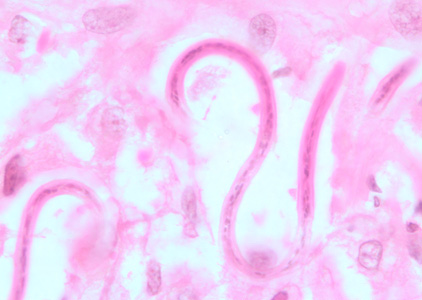

Trichinella spiralis